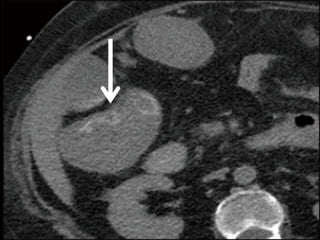

63-year-old woman status post aortic valve replacement who presents with a one

week history of abdominal pain becoming quite severe over the last 24 hours.

63-year-old woman statuspost aortic valve replacement who presents with a one week history of abdominal pain becoming quite severe over the last 24 hours.